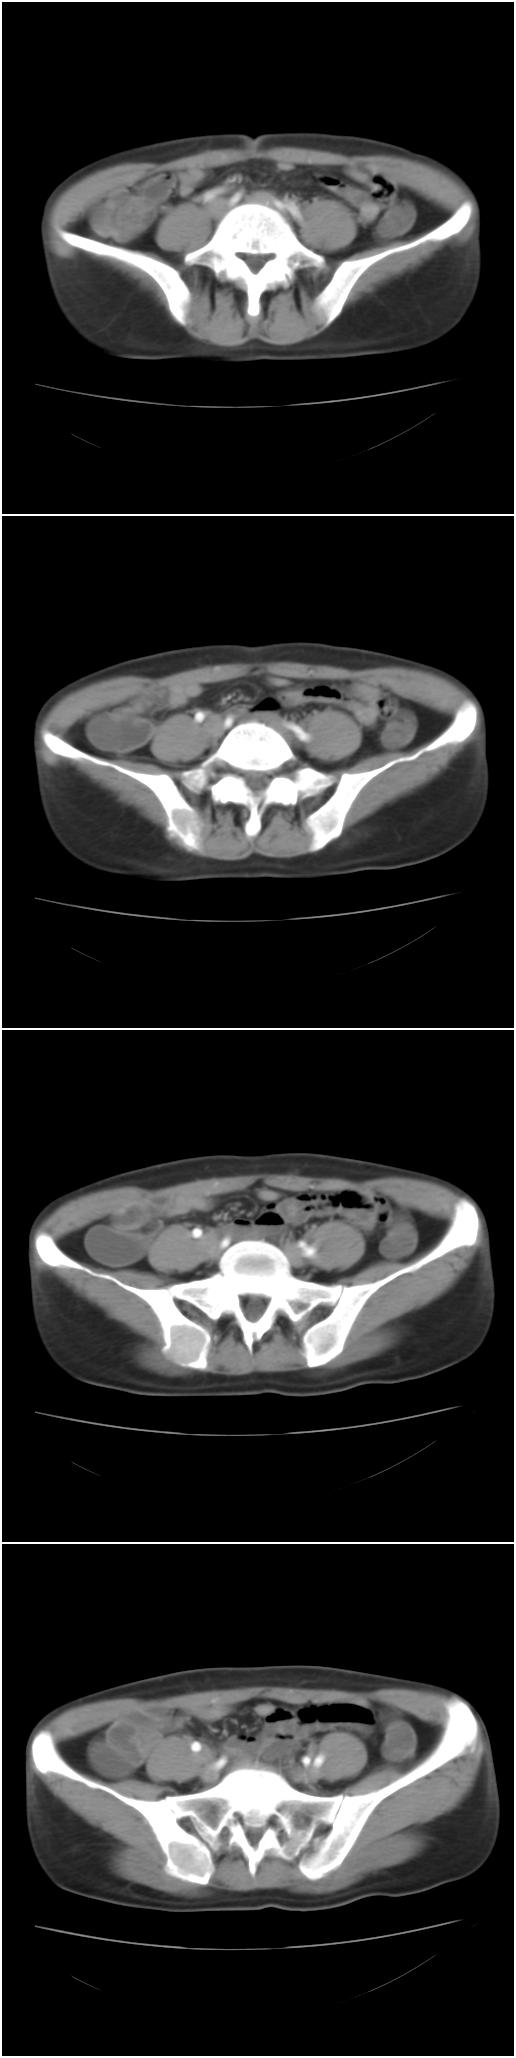

以下是今天的增强片,大家可以看看:

该病人今天做了增强,右侧髂骨病灶明显强化。

临床和影像学表现:女性患者46岁,有子宫肌瘤手术病史。影像所见可见残余宫颈部分,左右附件未见新生物;右髂骨翼后端囊状膨胀性骨破坏,囊性部分感觉有强化(楼主标上增强前后的ct值就很好了),未见明确的液—液平面,周边硬化不明显或轻度硬化。

分析:患者年龄46岁,没有明确外伤病史,病变呈膨胀性骨破坏,囊性部分未见明确的液—液平面,周边硬化不明显。综合分析该病例比较符合骨巨细胞瘤,不太符合动脉瘤样骨囊肿。

诊断:1、首先考虑骨巨细胞瘤;2子宫肌瘤术后改变